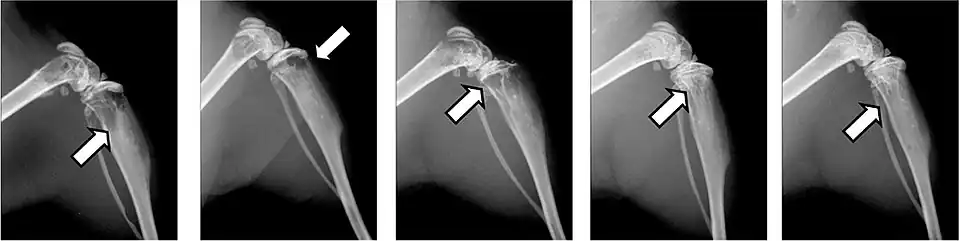

Fractures pathologiques

La fracture pathologique est une circonstance rare de découverte d'une métastase osseuse[75],[76].

Les fractures pathologiques sont des fractures de l’os qui surviennent sans atteinte extérieure, à cause d'un affaiblissement pathologique de la matrice osseuse. Les métastases surtout ostéolytiques, mais aussi parfois ostéocondensantes, affaiblissent l’os concerné qui selon les circonstances peut être sursollicité par des contraintes mécaniques faibles, et rompt. Ces fractures peuvent survenir dans des situations de tous les jours, comme le fait de se lever d'un siège ou de déplacer le patient[77]. Pour les métastases ostéocondensantes, l'épaisseur de l’os est certes augmentée, mais sa solidité est abaissée par sa construction complètement non structurée[6]. Dans le domaine de la colonne vertébrale, elles peuvent conduire à des enraidissements[65].

Les fractures pathologiques conduisent à des complications étendues et ont une influence considérable sur la qualité de vie et sur le pronostic. La durée de survie moyenne peut être diminuée de plusieurs mois[22]. Les bisphosphonates peuvent éviter dans bien des cas cette forme de fracture[78],[79].

Ce sont la plupart du temps les côtes ou les corps vertébraux qui sont atteints par les fractures. Les fractures dans les os longs, en particulier au col du fémur, présentent une gravité particulièrement élevée et sont le principal motif pour une intervention chirurgicale. Les fractures des corps vertébraux peuvent conduire à des syndromes de compression médullaire[65].

- Vues de fractures pathologiques

Fracture pathologique de l'humérus sur une métastase de carcinome du rein

Fracture pathologique du bras gauche sur une métastase osseuse de cancer du sein